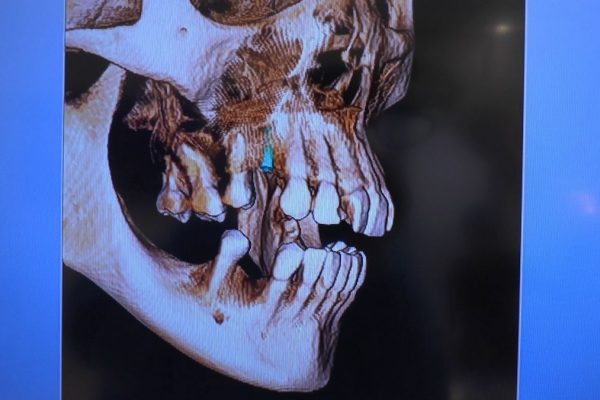

W ostatni weekend czerwca 2018 roku kursanci II Sezonu Preludium Implantologii odbyli piątą, finałową sesję, która w całości podporządkowana była praktyce. W ciągu dwóch dni zabiegowych Lekarze uczestniczący w szkoleniu przeprowadzili szereg zabiegów pod kierunkiem dr n.med. Violetty Szycik. Wszczepili 17 implantów oraz przeprowadzili ekstrakcje i zabiegi regeneracyjne kości. Zabiegi były wykonywane także w sedacji dożylnej z udziałem specjalisty anestezjologii i intensywnej terapii dr Jolanty Grzybowskiej. Preludium implantologii to nowy program edukacyjny dla adeptów implantologii stomatologicznej, którego celem jest wprowadzenie do implantologii poprzez pozyskanie wiedzy w szerokim zakresie i uwzględnieniem szczegółów mających decydujące znaczenie dla powodzenia leczenia implantologicznego. Ale tak jak wszystkie szkolenia w Instytucie Vivadental, w tym wiodące Practiculum Implantologii, zorientowane jest na praktyce i samodzielnym wykonywaniu zabiegów pod kierunkiem Mentora. To najlepsza edukacja w medycynie zabiegowej, a zarazem najlepszy start do implantologii.